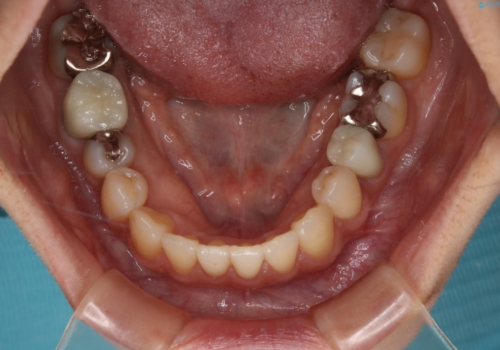

前歯が内側に入っている:インビザライン治療

- 上の前歯は内側に入っていることが気になりご相談にいらした方です。インビザラインにて治療を行いました。

1週間でのマウスピース交換を指示していましたが、20時間以上使えない時があると不安との事で、2週間ごとの交換にしていました(実際はほとんど20時間以上使用できていたようです)。治療終了まで時間はかかりましたが、最終的に綺麗に並べることができ、大変喜んでいただけました。